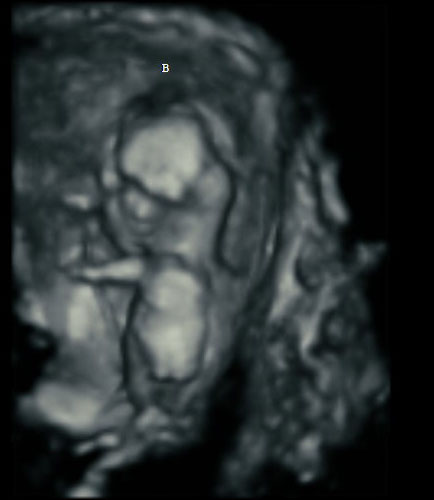

Here’s how ultrasound works in pregnancy: As early as 16 weeks, women can see a “fetal portrait” of their baby and determine its gender. Ultrasound technology has improved dramatically over the decades from flat, grainy black and white images to the current three-dimensional time experience.

Most hospitals offer some 3D scanning, but 3D ultrasound produces images that show the width, height and depth of a developing child. Rather than sending sound waves straight into the womb and recording when they bounce back as is common in 2D imaging, 3D ultrasound sends sound waves from different angles. A computer then renders a 3D image based on this data.

4D ultrasound adds movement as it occurs. The fourth dimension is time. You’re actually watching your baby live in 3D mode. How cool is that?